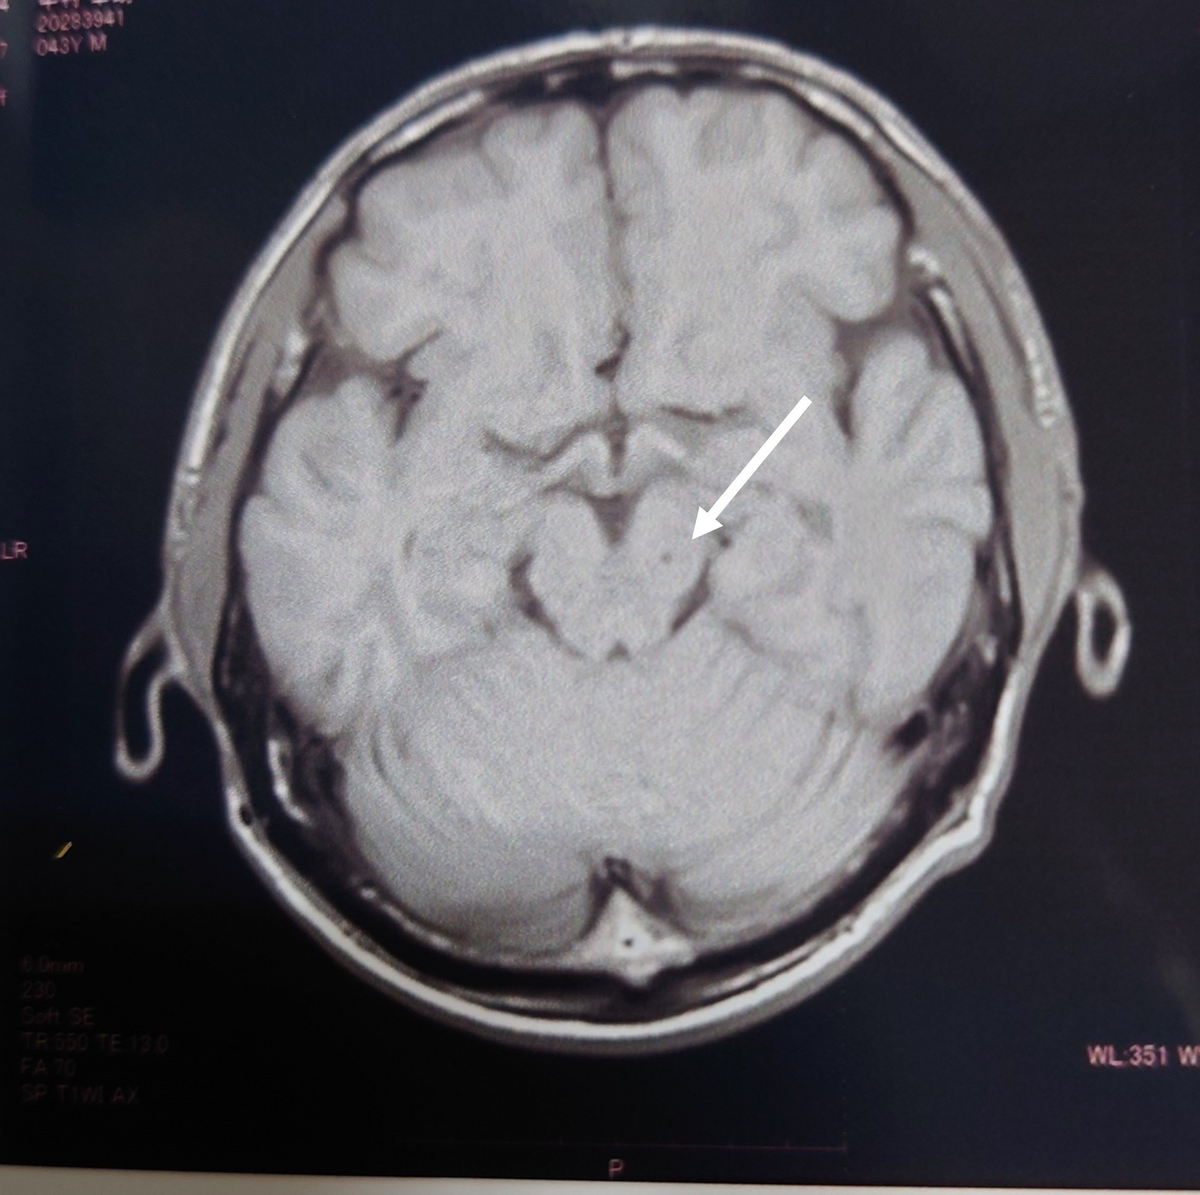

↓2019年の画像

2020年の画像

2023年の画像(病院が違います)